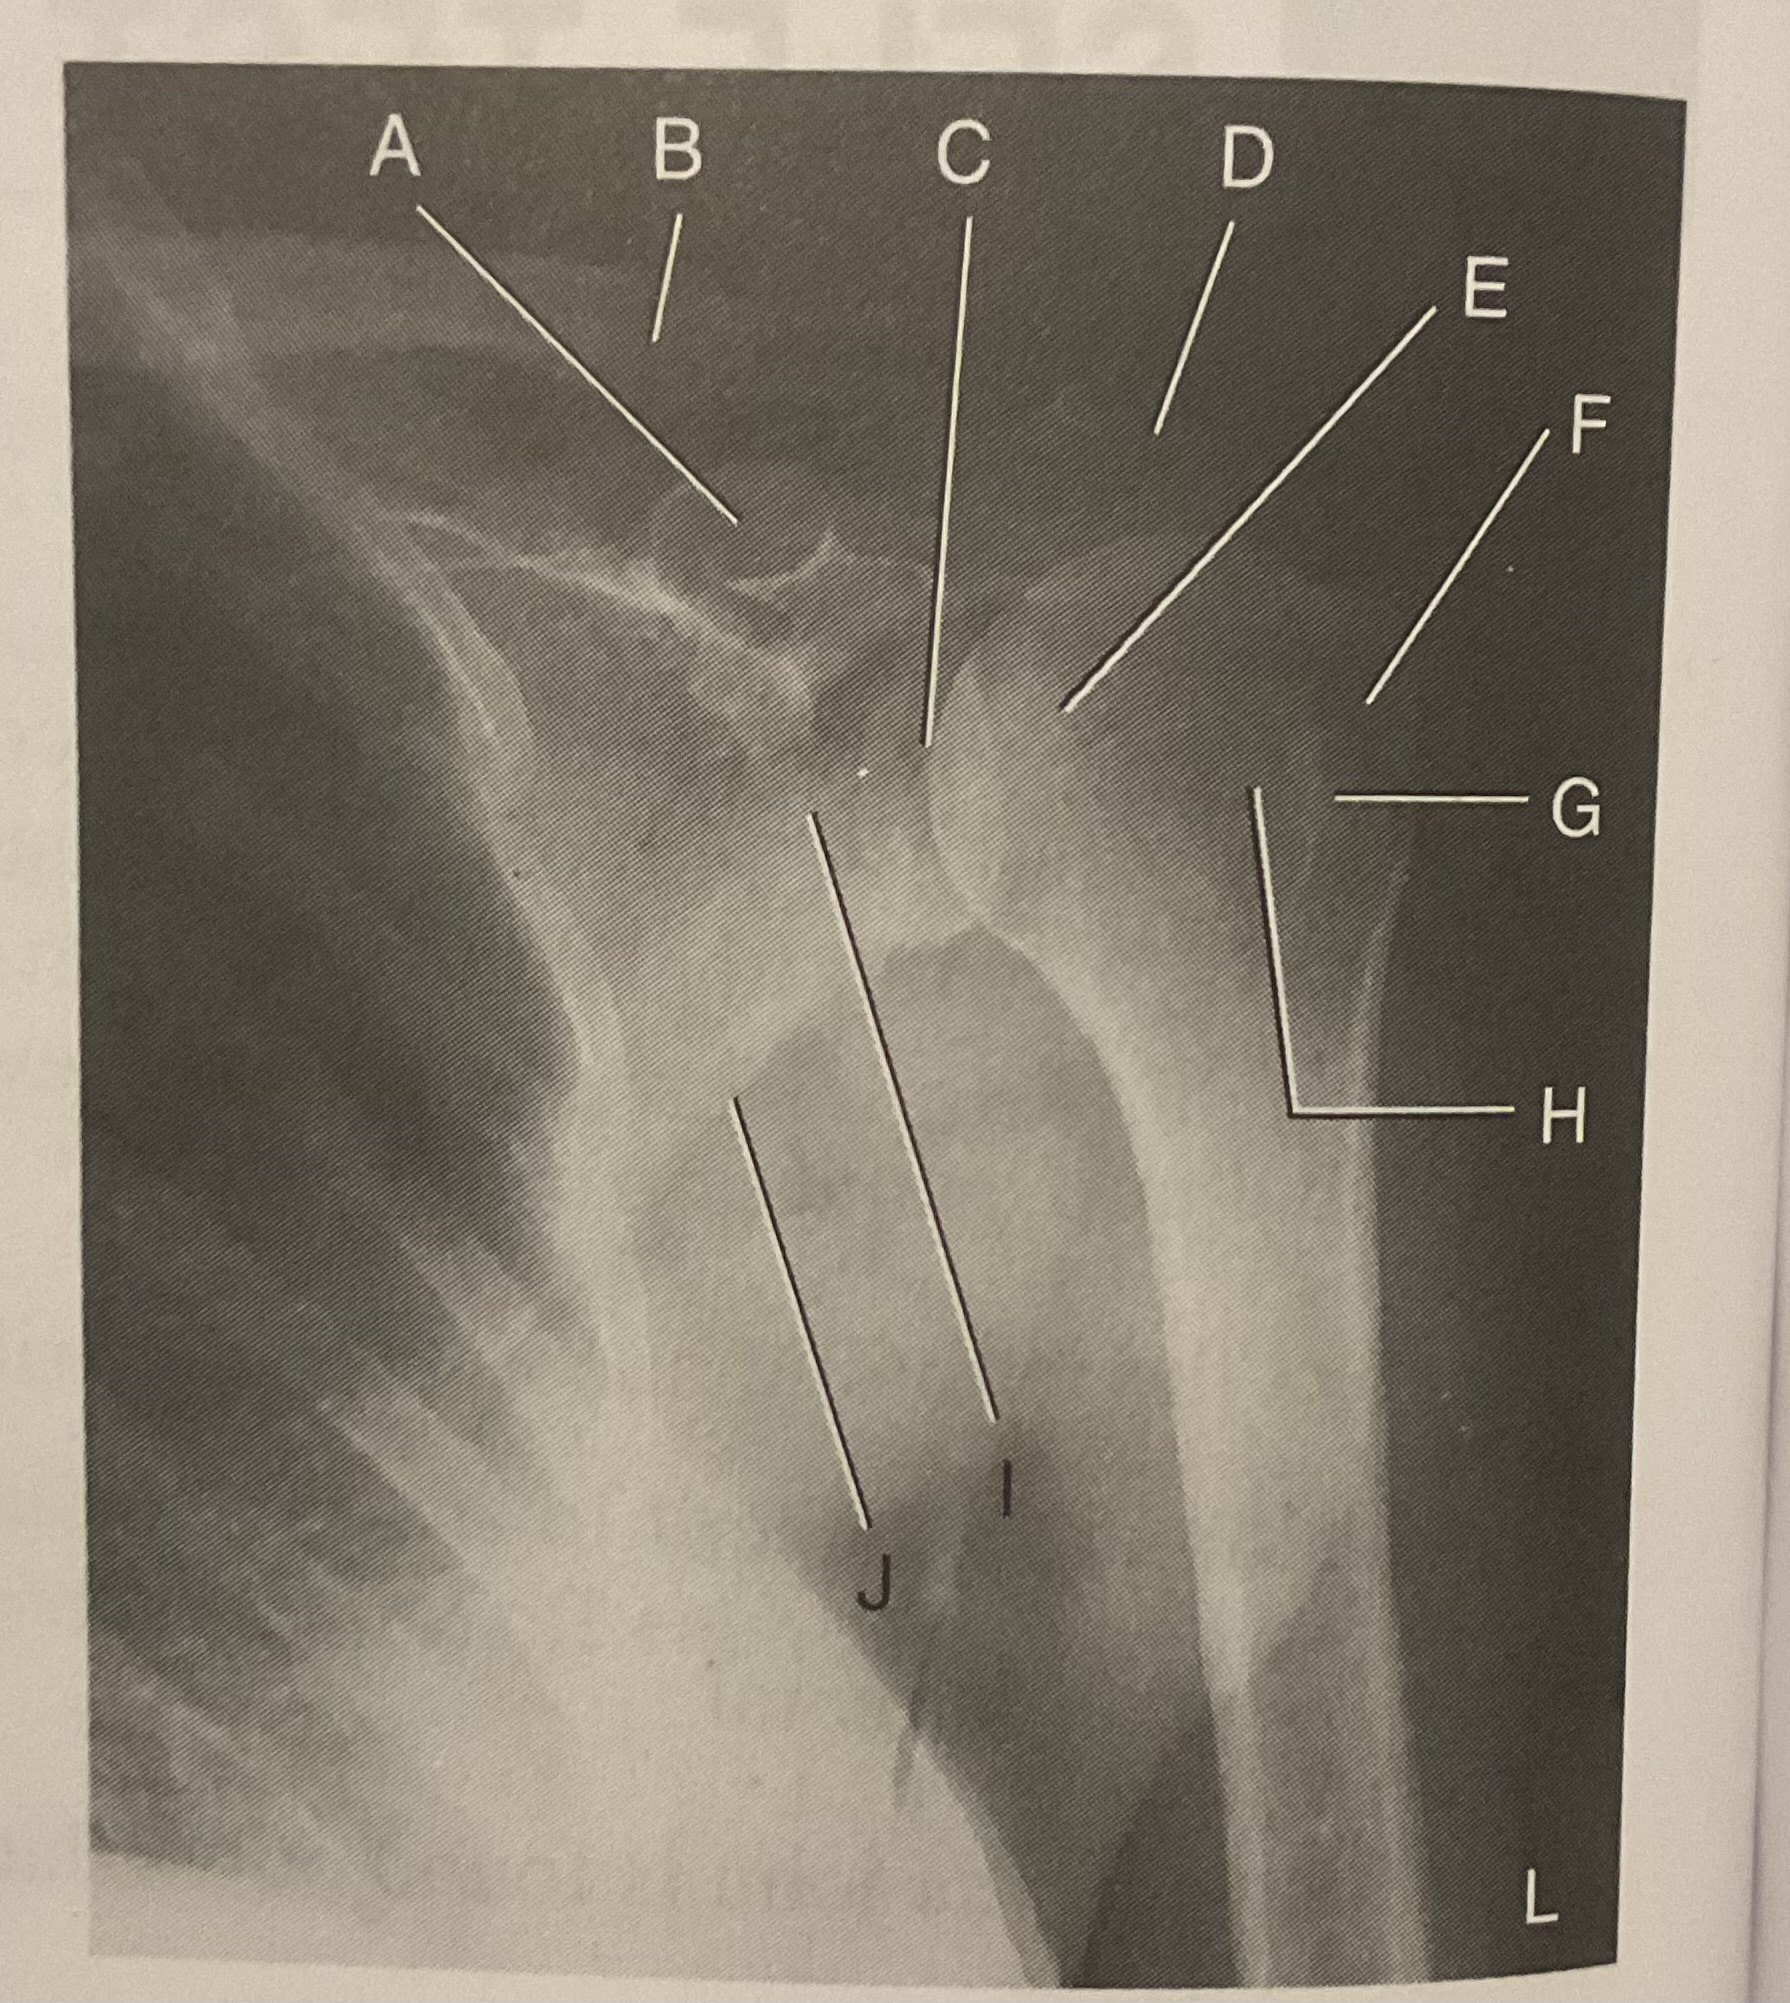

A?

Coracoid process

B?

Clavicle

C?

Scapulohumeral joint

D?

Acromion of scapula

E?

Head of humerus

F?

Greater tubercle

G?

Intertubercular sulcus

H?

Lesser tubercle

I?

Neck of scapula

J?

Lateral (axillary) border of scapula

What AP projection does this image represent?

External